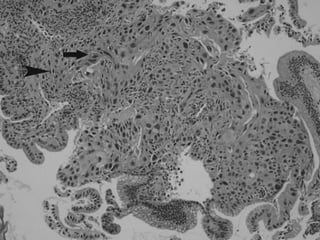

Magnification X 100000

Cell size